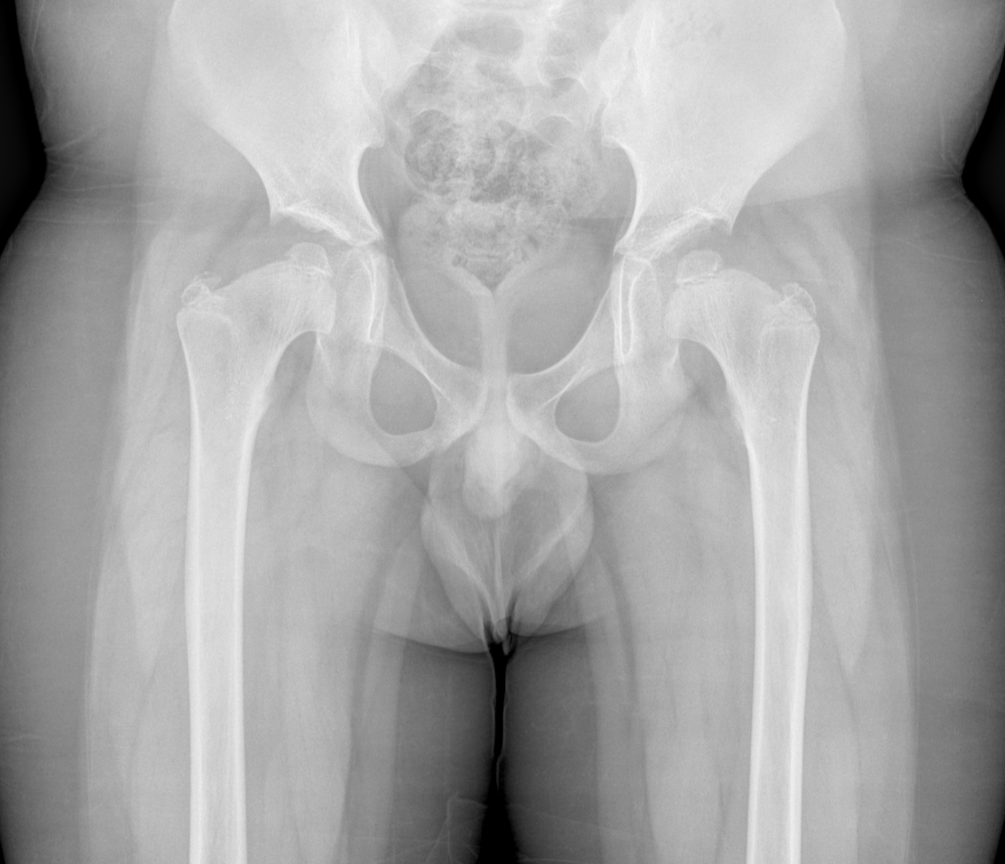

3. Multiple epiphyseal dysplasia